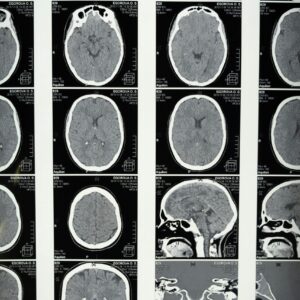

Advanced Diagnostics at Your Fingertips

At our hospital, we have real-time laboratory tests, ECG, X-ray, and ultrasound facilities for fast and accurate results, aiding our doctors in making prompt treatment decisions.